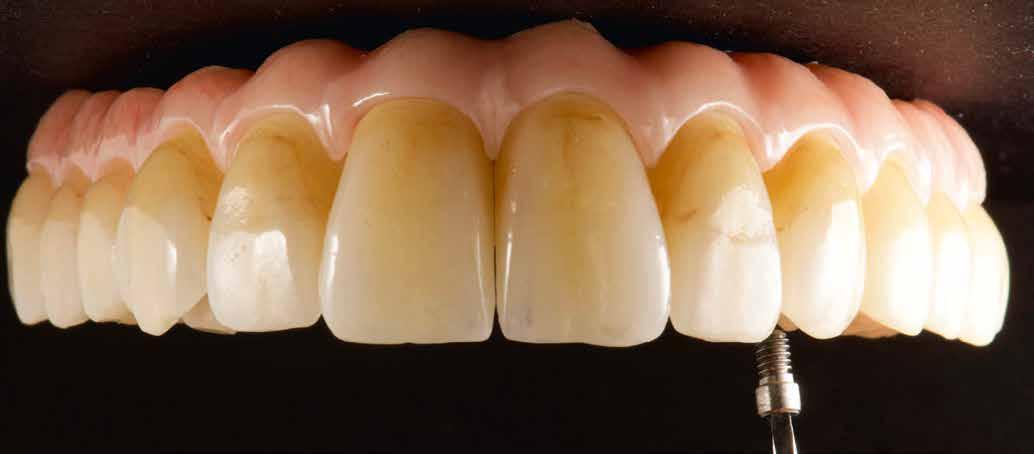

Interdiszciplináris fogászati kezelés myofunkcionális készülék, alignerek és protetikai ellátás alkalmazásával

MED. DENT Abradált frontfogakkal rendelkező felnőtt páciens interdiszciplináris kezelése